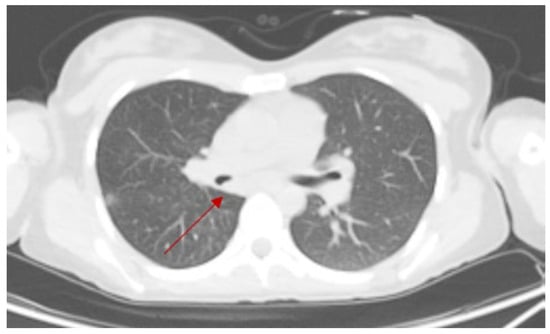

4.1. Case 1